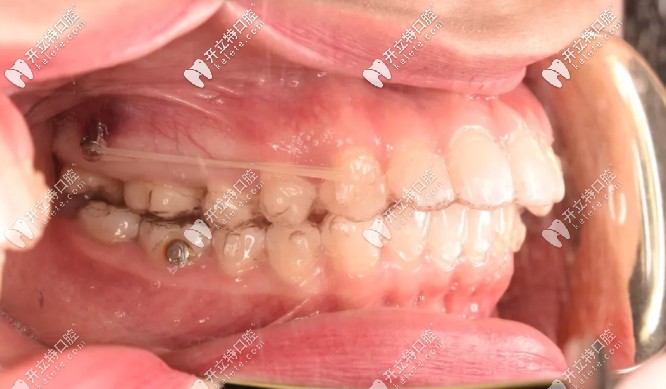

為了不拔牙,在設(shè)計方面時就溝通了打骨釘,我是在第18副的時候打的骨釘,看圖▼